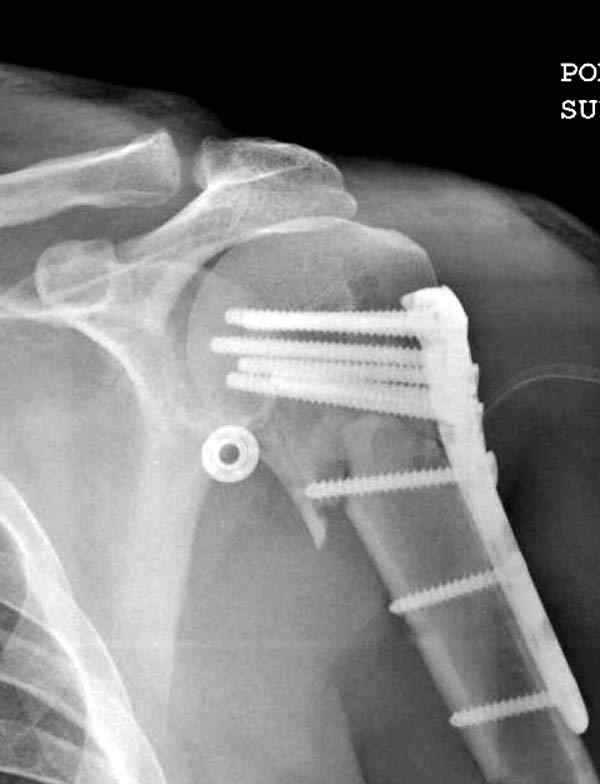

Пациентка Б.1953 г.р., врач-терапевт. Травма 27.11.08г. Падение с высоты роста. Выявлен закрытый не осложненный оскольчатый перелом хирургической шейки левого плеча со смещением. 02.12.08г. оперирована. Выполнена открытая репозиция и остеосинтез пластиной LCP Деост с дополнительной фиксацией отдельно лежащего фрагмента винтом. Послеоперационный период протекал без особенностей, заживление раны первичным натяжением. Швы сняты через 10 дней. Иммобилизация левой верхней конечности клиновидной подушкой 4 недели. По окончании срока – рентген-контроль и умеренная разработка плечевого сустава. В течении месяца функция левого плечевого сустава восстановилась удовлетворительно: поднятие руки до 110 гр., отведение - 90 гр. и до 110 гр. отведение с лопаткой. Отведение руки назад – 20 гр. Наружная и внутренняя ротация – 20 гр. Пациентка по настоянию самостоятельно вышла на работу. 27.03.09 при контрольном осмотре жалоб не предъявляет, болевой синдром в левом плечевом суставе отсутствует. Отведение плеча активно до 90 гр, пассивно с лопаткой до 110 гр., поднятие – 110 гр, отведение назад 20 гр, наружная и внутренняя ротация по 20 гр. На контрольных рентгенограммах отмечается смещение металлоконструкции, ротация головки плеча с приведением дистального отломка на 13 гр. и смещением к зади на 30 гр. Рентгенограммы прилагаются. Ваш взгляд на дальнейшую тактику лечения пациентки?

Ни какой миграции и смещения пластины нет, это изначальные смещения при остесинтезе.

Нет аксиальной проекции сразу после вмешательства. Возможно, никакого значительного смещения нет, все осталось так, как первично сопоставили...и,

Уважаемый Евгений, похоже, что первый и второй Р-снимки выполнены несколько в разных положениях(ротация) плечевой кости, в связи с этим создается впечатление смещения пластины. Остеосинтез выполнен при угловом смещении отломков.Таковым и остался. Данная ситуация была бы очевидна гораздо раньше, если бы при контрольной Р-графии были выполнены снимки в 2-х проекциях.(Не в обиду, сам иногда выполняю только один).

Здесь пример открытой репозиции 57 летнего с переломом плеча (1,2) смещение обнаружено на интероперационном снимке. При нормальной прямой проекция (3) угловое смещение обнаружили в аксиальной проекции (4)

После устранения смещения пластина установлена выше (5,6,7) и финальные снимки (8,9,10)